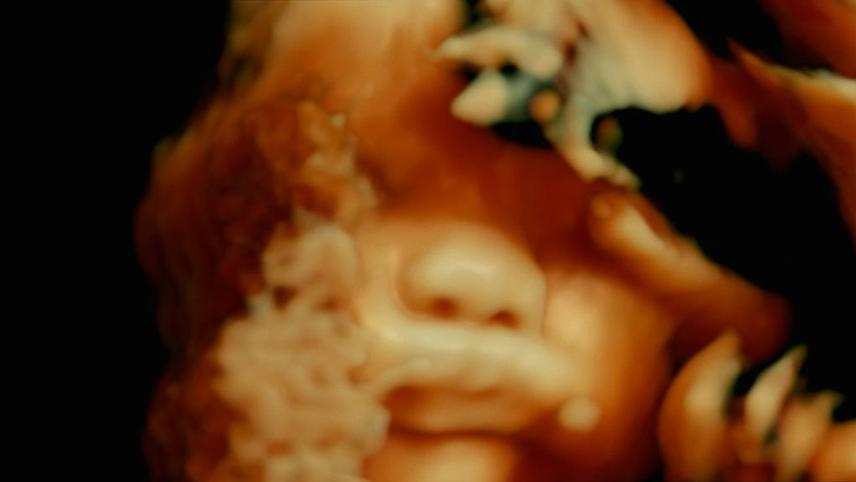

DE HUMANI CORPORIS FABRICA es un documental filmado en varios hospitales de París a través del punto de vista de decenas de herramientas médicas, que busca explorar la fragilidad de nuestros cuerpos, pero también el tenso y agotado sistema de salud francés.

DE HUMANI CORPORIS FABRICA - 22 de mayo